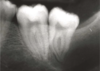

What radiographic sign is this showing in regards to M3M surgery risk to ID canal

Diversion / deflection of ID canal

26

Darkening of the root where crossed by the canal

27

Interruption of white lines / lamina dura of the ID canal

28

Deflection of the root

29

Narrowing of ID canal

30

Narrowing of root

31

Dark + bifid root (root appears to split / divide over ID canal)

32

Juxta Apical Area